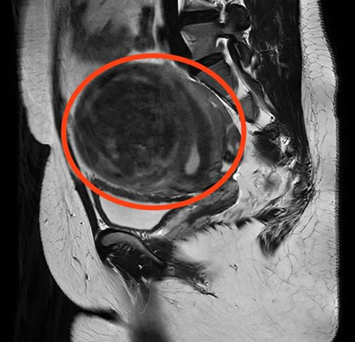

妇科门诊就诊。经过B超检查显示,曹女士子宫左侧壁肌瘤内可见102*88*92mm的包块,考虑为子宫肌瘤。面对如此“巨大”的肌瘤,曹女士忧心忡忡,以为只有通过开腹手术才能将其切除,手术过程及术后遗留的疤痕让她既害怕又焦虑。

CT检查显示子宫左侧壁巨大肌瘤

妇产科三区主治医生胡媛耐心地安抚曹女士,并为她详细讲解了治疗方案。“结合您的B超及CT结果,我们只需要进行一个小小的微创手术,就能把肌瘤切掉。而且,手术切口在肚脐眼,这里天然隐蔽,等伤口痊愈以后,几乎不会影响腹部美观。”胡媛医生的这番话,让曹女士悬着的心终于落了地。